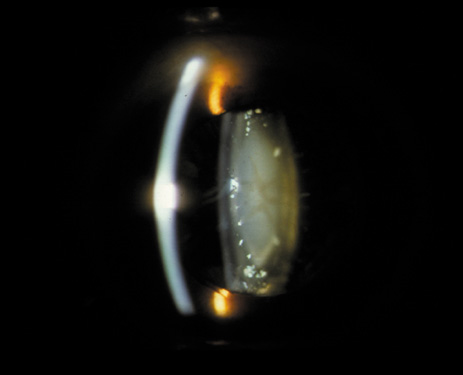

PSC may also result from irradiation or steroid ingestion, or it may be associated with diabetes, high myopia,37–41 retinal degeneration (e.g., retinitis pigmentosa),42,43 and gyrate atrophy.44,45 In some cases, the PSC eventually may be pushed to the cortex as new fibers are laid down and the offending agent is no longer present (Fig. 16A and B).

Fig. 16. A: Scheimpflug slit image of two types of PSCs (steroid-induced and gyrate atrophy-related) showing the positions of the opacities. B: Densitometry profiles showing the position of the gyrate atrophy-related PSC in comparison with the steroid-induced PSC. These suggest that the PSC migrates anteriorly as the newly laid down fibers push the PSC deeper into the cortex.45